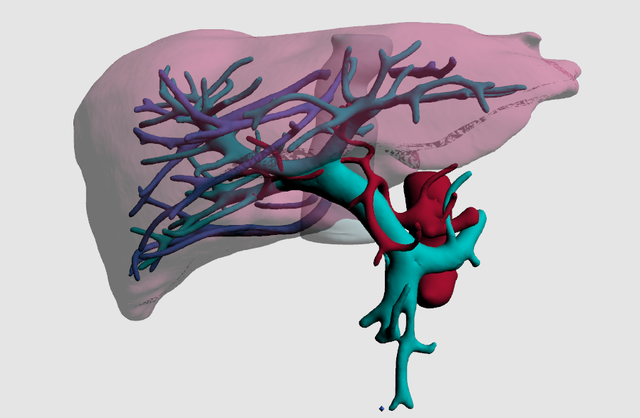

(六)手术治疗

对于少部分经过良好膳食控制的患者,但是仍然频繁发生严重代谢失代偿的,以及既往有同胞死亡或者有心肌病的PA患者,可以考虑进行肝移植的治疗。